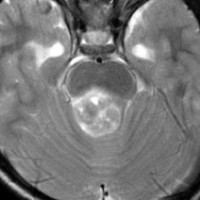

脳幹部から発生した退形成性神経節膠腫 grade 3

軽い右顔面神経麻痺で発症した小児で,右上下肢の軽度の失調症もありました。脳幹部(橋)の右背側から発生した腫瘍で,軽度の閉塞性水頭症を合併しています。左はT2強調画像で,橋の右側ににじむような浸潤像と浮腫があります。腫瘍は小嚢胞を形成してT2強調画像で実質は等信号です。真ん中の画像はCISS画像で橋が腫大しているのがよくわかります。右側はガドリニウム増強像で,全体が増強されてまだらな増強所見となっています。正中後頭下開頭で全摘出 gross total removal して,局所放射線治療とtemozolomide, cisplatine, etoposide, gleevec, hydoreaなどの化学療法を行いましたが,手術後4ヶ月で激しい播種再発を来しました。